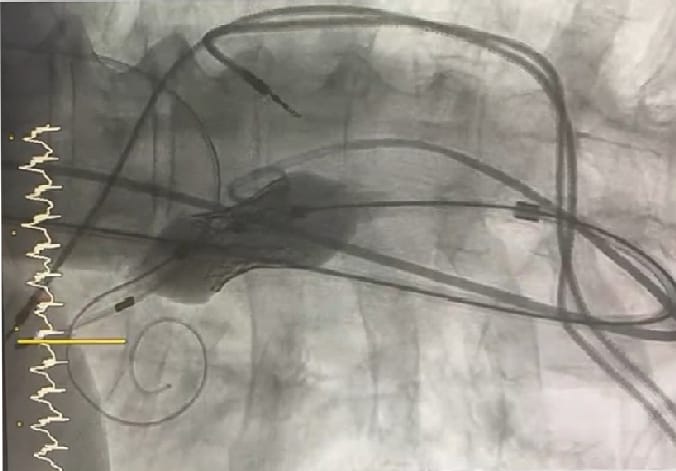

تمكَّن فريق القسطرة في مستشفيات المركز التخصصي الطبي (فرع الملك عبدالله)، بإشراف كل من رئيس القسم الدكتور علي المسعود، والدكتور باسل السباتين، من إجراء عملية استبدال وتركيب للصمام الأورطي لمواطنة سبعينية عن طريق القسطرة التداخلية، دون اللجوء لعملية القلب المفتوح، التي تعتبر عالية الخطورة على المريضة.

علمًا بأن عملية تغيير الصمام الأورطي عن طريق القسطرة تعتبر من أحدث التقنيات العالمية في مجال صمامات القلب، وتتم بدون جراحة قلب مفتوح، التي تحمل مضاعفات جانبية.

وقد تم في العملية استخدام نوع جديد من الصمامات الأورطية لأول مرة في القطاع الصحي الخاص.